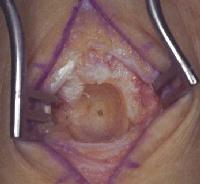

Clinical Example: Giant cell tumor of the dorsal wrist resembling a dorsal wrist ganglion

Giant cell tumors are the most common solid tumor involving the dorsum of the hand. The majority arise in the soft tissues. Although slow growing, they are prone to recurrence, and require agressive local excision and long term followup.

Sure looks like a dorsal wrist ganglion...However, it was too lumpy, and didn't transilluminate.